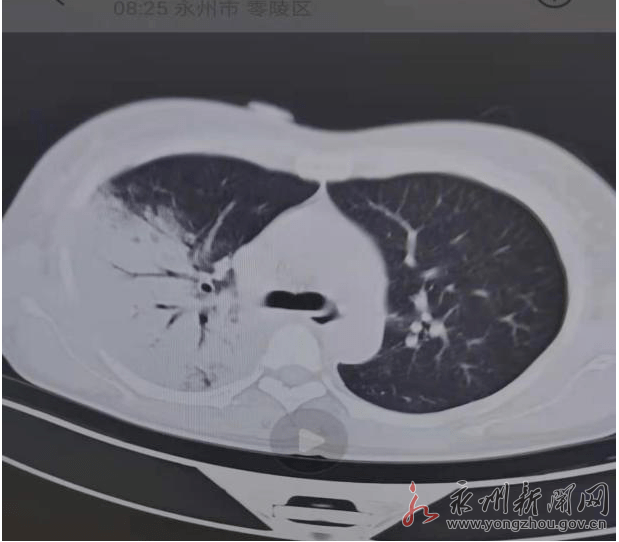

永州市第四人民医院治愈一例鹦鹉热衣原体感染患者

图片尺寸619x542